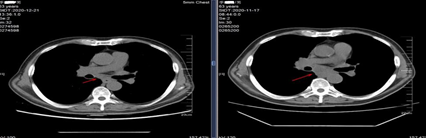

一个月以后复查的CT结果显示,患者好转,心包积液消失,两侧胸水消失,病灶仍然存在。

复查CT对比图